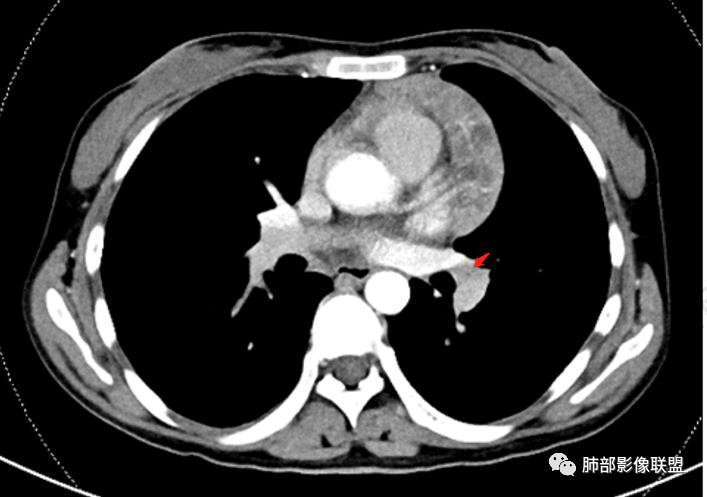

2.影像显示前纵隔不规则块状影,依势贴附心脏大血管旁,密度不均,边界不甚清楚,有结节融合感。

3.病灶轻度不均匀强化,可见血管穿行,散在液性低密度区。

双肺门未见肿大淋巴结。

4.双侧腋窝区见增大淋巴结,边界清楚。

1.年轻女性,前纵隔不规则块状影,密度不均,边界不甚清楚,有结节融合感,轻度不均匀强化,可见血管穿行,最常见最符合的无疑是淋巴瘤!

前纵隔和双侧腋窝多发的淋巴结肿大,前纵隔为甚,融合呈中等强化,部分坏死呈低密度,包埋肺动脉主干和左心缘,融合斑块状,内见血管飘浮特点,前纵隔脂肪间隙混浊,首选淋巴瘤!